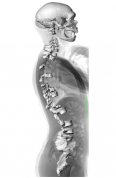

Reconstruction of the La Chapelle-aux-Saints Neanderthal spine superimposed onto the radiograph of a modern human

Martin Haeusler, University of Zurich